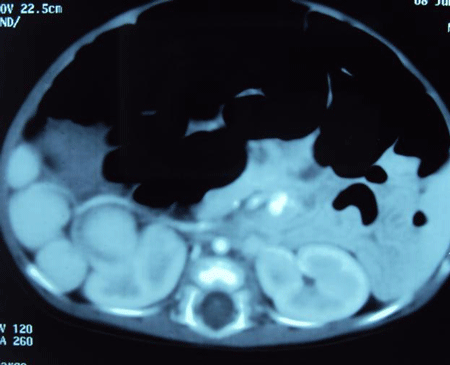

A 1-month-old female child presented with jaundice, clay colored stools and dark yellow urine since the first week of life. There was no history of fever and cyanotic spells. She was born full term via a normal vaginal delivery and was first in birth order. There was no consanguinity among the parents. Physical examination revealed jaundice, normal facies and no organomegaly. She was hemodynamically stable. She was put on phenobarbitone and vitamin K on the lines of treatment for cholestatic jaundice. There was some improvement in color of stools and icterus after 5 days of therapy. In paraclinic evaluation, hemoglobin was 9.8 gm%, TLC 13,200/mm, total and direct bilirubin were elevated (total bilirubin 4.64 mg/dl, and direct bilirubin 2.5 mg/dl) and was in favor of cholestasis. Liver enzymes were elevated (SGOT-165 IU/L and SGPT-77 IU/L). Alkaline phosphatase was markedly raised, 1991 IU/L (normal up to 300). Total serum protein (5.2 gm%)and albumin(3.3 gm%) were below the normal range. Prothrombin time (PT) and INR were corrected. Radiographs of chest and abdomen revealed dextrocardia and liver shadow in the left side. Abdominal ultrasound showed liver in the left, stomach in the right side of abdomen and situs inversus. Spleen was not visible, instead multiple rounded masses along splenic vessels were presented on right side, suggestive of polysplenia. Gallbladder was not visualized on ultrasound of the abdomen and IHBR were not dilated. Triangular cord sign in liver hilum could not be elicited. CECT confirmed the above findings (Fig. 1) and revealed situs inversus totalis. With well tampered Hepatobiliary iminodiacetic acid (HIDA) scan no excretion of the radiopharmaceutical tracer was noted. This data was highly suggestive of biliary atresia (BA). Hepatoportoenterostomy (Kasai) operation was planned. At operation, the liver was seen on left side, and looked cirrhotic, gallbladder was absent, common hepatic duct, right and left hepatic ducts were atretic. Stomach was on right side. Multiple spleens / polysplenia (21 splenicules), floating and non-floating were present on the right side of the abdominal cavity (Fig. 2) and there was Typical variety of malrotation. The diagnosis of Biliary Atresia associated with polysplenia syndrome, dextrocardia, situs inversus totalis and malrotation of intestine was made.

Figure 1: CT scan showing multiple splenicules. |